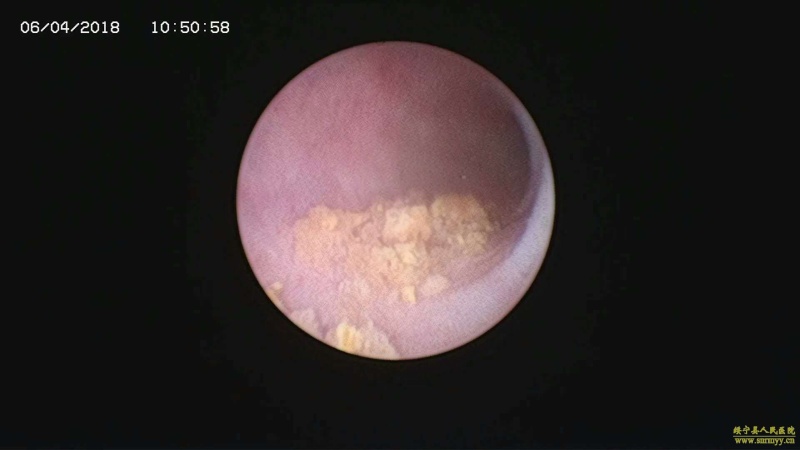

多镜联合治结石 4月6日,处于休假期间,但绥宁县人民医院泌尿外科的医护没有休息,在科主任张华生的带领下,打破常规,挑战高度,成功完成了一台复杂的结石手术。 据悉,患者姓杨,是一位60岁的男性患者,因"间断性左侧腰痛2年,再发伴尿痛2天"入院,经检查后发现患者左肾、左侧输尿管、膀胱内均有多发结石。针对这种结石,传统的手术方法至少需要开3刀,且需分期进行,使得患者痛苦大、治疗周期延长,费用也相应增高。肾结石开刀手术后劳动力会严重散失,即使采用现在流行的微创手术,常规也得分期进行,患者免不了多次手术的痛苦。为进一步减轻患者痛苦,绥宁县人民医院泌尿外科的医师们经过慎重考虑,决定打破常规,制定了多镜联合取石的手术方案。手术在4月6日顺利进行,术中联合膀胱镜、输尿管镜、经皮肾镜进行了长达70分钟的治疗,使得出血量不超过5mL且伤口仅0.5cm,一次性将患者膀胱,左侧输尿管,左肾结石全部取出。术后第五天经复查无任何结石残留,4月13日患者顺利出院。 目前,绥宁县人民医院泌尿外科在微创手术治疗各种尿路结石的技术上,己非常熟练。结石在整个邵阳地区发病率都很高,平常多喝水,每天饮水2000ml以上,调节饮食生活习惯,坚持锻炼可以有效预防结石发生,定期的健康体检也是预防结石的有效措施之一,可以早期发现结石,及时治疗。(图文 付志峰 编辑 谢雅玲) 图为:泌尿外科主任张华生、副主任付志峰进行手术时场景 图为:膀胱结石显象→手术碎石中显像→膀胱结石碎石后显像 图为:输尿管结石显像→输尿管结石碎石后显像 图为:肾结石显像→取出的肾结石标本 图为:术中建立穿刺通道 图为:术后留置的引流管 图为:术后伤口情况 |